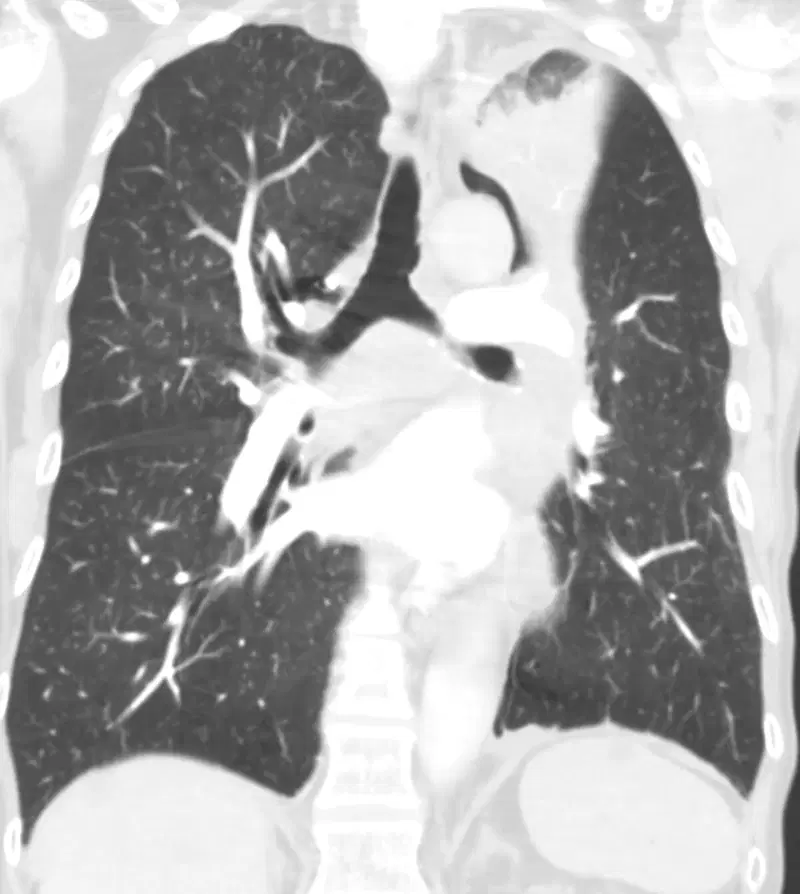

The Luftsichel sign is caused by collapse of the left upper lobe of the lung, most commonly due to bronchogenic carcinoma, mucus plugging, or other obstructive processes. This results in volume loss and atelectasis of the left upper lobe, with compensatory hyperinflation of the superior segment of the left lower lobe. It is most frequently associated with left upper lobe collapse but can also be seen in conditions causing a para-aortic air crescent, such as pneumomediastinum or right lung herniation.

The collapse of the left upper lobe causes the atelectatic lobe to shift laterally and medially toward the left heart border, obliterating its normal silhouette on the frontal chest radiograph. Meanwhile, the superior segment of the left lower lobe becomes hyperinflated and extends between the collapsed lobe and the aortic arch, producing a crescent of lucency adjacent to the aortic knob. This hyperinflated segment forms the visually distinctive air crescent or “Luftsichel“, representing interposition of aerated lung tissue between the mediastinum and the collapsed upper lobe.